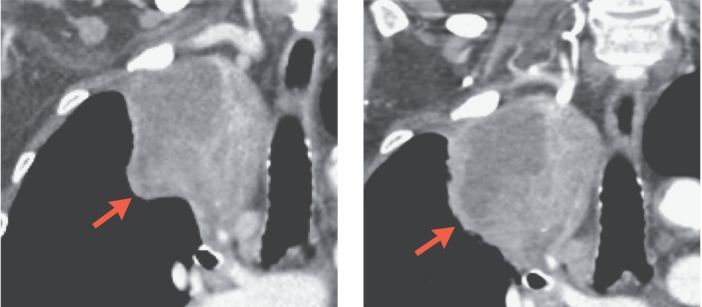

21位患者,在接受O药治疗前,在接受O药治疗后又尚未接受手术前,拍了两次片子。结果提示:2名患者肿瘤明显缩小、18名患者肿瘤稳定、1名患者肿瘤进展,从影像学上判断,术前用1-2次PD-1,疾病控制率是96%!

下图展示了其中一位病友在用药前后肿瘤的明显缩小:

初始影像 手术前PD-1治疗第四周